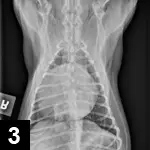

Obstructive shock is caused by any obstruction or maldistribution of blood flow that results in a decreased preload and subsequent decreased cardiac output. Causes of obstructive shock include gastric dilatation–volvulus (GDV), caval syndrome from heartworm disease, and pericardial effusion (Figure 3). Therapy involves identification and correction of the underlying cause of the obstruction—for example, stomach decompression in GDV or pericardiocentesis for pericardial effusion. Similar to hypovolemic shock treatment, IV fluid therapy can be beneficial for cases of obstructive shock.

A radiograph shows a canine thoracic cavity with clear visibility of the heart, lungs, and spine. The image highlights the diaphragm and surrounding structures, providing insight into the animal's respiratory and cardiovascular health.

Figure 3 Ventrodorsal thoracic radiograph with severe, globoid cardiomegaly